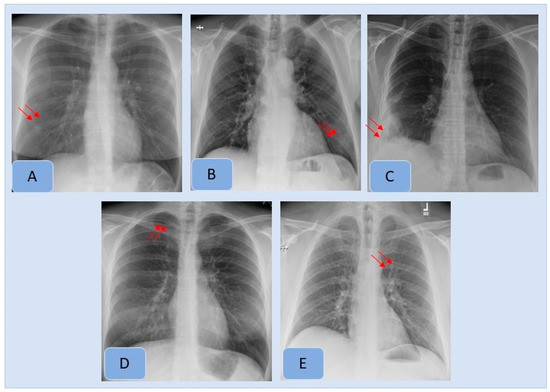

Figure 3. Examples of clinically important missed findings on CXRs included in our study. These included pulmonary nodule (A), consolidation (B), pleural effusion (C), pneumothorax (D) and hilar prominence (E).

With the ground truth, there were 410 CXRs (17.1%, 410/2407), with missed findings in 342/2407 CXRs (14.2% missed finding rate). The most frequent missed findings included lung nodules (n= 177/410, 43.1%), subsegmental atelectasis or scarring (n = 67/410, 16.3%), consolidation (n = 62/410, 15.1%), enlarged cardiac silhouette (n = 35/410, 8.5%), mediastinal widening (n = 24/410, 5.8%), hilar enlargement (n = 19/410, 4.6%), rib fractures (n = 11/410, 2.7%), pleural effusions (n = 11/410, 2.7%) and pneumothorax (n = 4/410, 0.1%). Figure 3 presents examples of missed findings on CXRs.